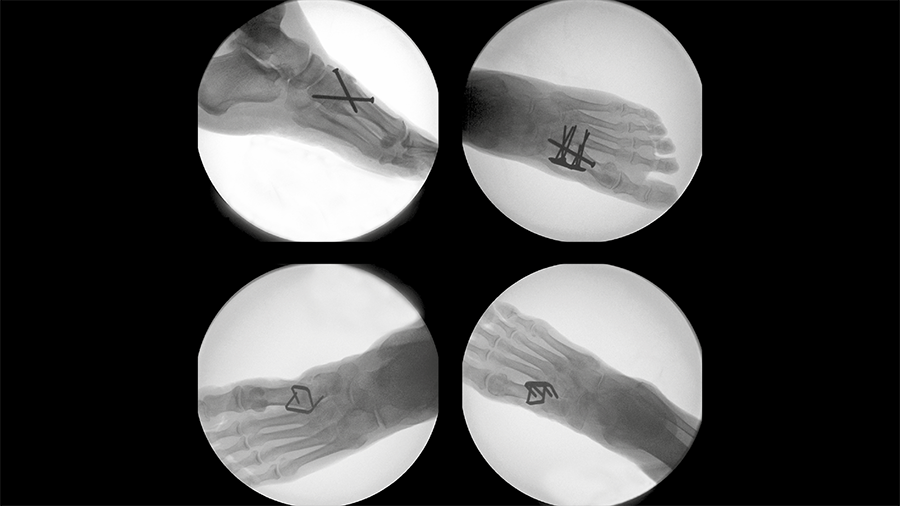

The implant system is delivered to the operating room in a disposable, sterile kit containing the Insertion Stick with the pre-loaded implant (Fig 2) and other instruments needed for the implantation procedure (Fig 3).

Once the DPS Hammertoe CCI is inserted into the bone and released from the Insertion Stick, the implant attempts to regain its original shape with converging legs thereby providing active continuous compression at the fusion site (Fig 4). The design with the four legs orthogonal to the bone axis and the active compression feature are beneficial for the distraction resistance (Fig 5).

The implant is not supposed to be reused after it has been discharged from the Insertion Stick because any processing, reprocessing, or mechanical manipulation may reduce the effectiveness of the implant.